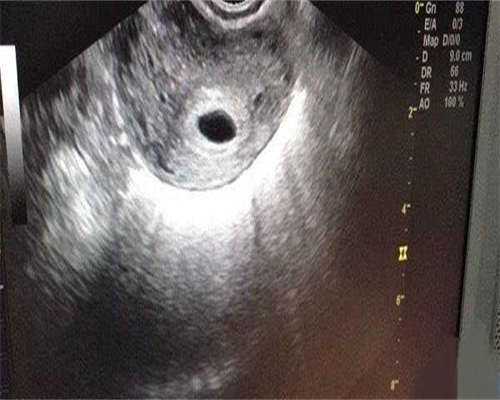

卵巢囊肿,尤其是子宫内膜异位囊肿(巧克力囊肿)的剥除手术,在去除病灶的同时,不可避免地会带走一部分正常的卵巢皮质组织,并可能影响卵巢的血流供应。许多姐妹在术后复查时会发现,反映卵巢储备功能的AMH(抗缪勒管激素)值出现显著且不可逆的下降,甚至面临卵巢早衰的风险。这是我们需要共同面对的现实。

手术后基础卵泡数量减少是常见的现象。此时,我们必须深刻理解:试管成功的关键在于“卵子质量”而非“数量”。一枚染色体正常、胞质能量充沛的高质量卵子,其孕育生命的潜力远胜于数枚质量不佳的卵子。临床上有许多案例证明,即使最终只获得1-2枚优质卵子,成功受孕并生下健康宝宝的几率依然非常可观。所以,不要因为获卵数少而气馁,质量才是王道。